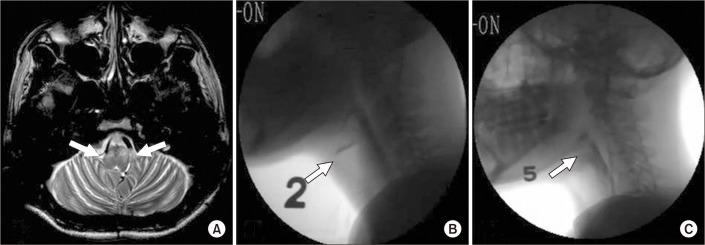

行为治疗联合丙戊酸治疗中风患者腭肌阵挛所致吞咽困难的有效性:两例报告

Effectiveness of Combining Behavioral Treatment With Valproic Acid for Dysphagia Caused by Palatal Myoclonus in Patients With Stroke: Two Case Reports.

Palatal myoclonus (PM) is a rare disease that may induce dysphagia. Since dysphagia related to PM is unique and is characterized by myoclonic movements of the involved muscles, specific treatments are needed for rehabilitation. However, no study has investigated the treatment effectiveness for this condition. Therefore, the aim of this case report was to describe the benefit of combining behavioral treatment with valproic acid administration in patients with dysphagia triggered by PM. The two cases were treated with combined treatment. The outcomes evaluated by videofluoroscopic swallowing studies before and after the treatment showed significant decreases in myoclonic movements and improved swallowing function. We conclude that the combined treatment was effective against dysphagia related to PM.

摘要

腭肌阵挛(PM)是一种可能导致吞咽困难的罕见疾病。由于与PM相关的吞咽困难具有独特性,其特征为受累肌肉的肌阵挛运动,因此康复需要特定的治疗方法。然而,尚无研究调查过针对这种情况的治疗效果。因此,本病例报告的目的是描述行为治疗与丙戊酸给药相结合对由PM引发吞咽困难患者的益处。这两个病例接受了联合治疗。治疗前后通过电视荧光吞咽造影检查评估的结果显示,肌阵挛运动显著减少,吞咽功能得到改善。我们得出结论,联合治疗对与PM相关的吞咽困难有效。